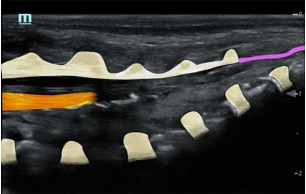

Sonoanatomy

Ultrasound probe selection: linear high frequency probe

Mapping/scout scan: look between the intervertebral spinous processes and laminae:

1)Probe position transverse over the sacral cornua (-> frog’s eyes US view)

2)Then rotate probe 90 degrees for a longitudinal view

Identify:

•Sacral cornua

•Sacrum

•Sacrococcygeal membrane

•End of the dural sac (hyperechoic (<-> CSF are anechoic (black)

•Caudal epidural space

•Assess the position of the dural sac in relation to the sacrococcygeal membrane

NOTE: Ultrasound can't see through bone; so with increasing age (= increasing angulation of the spinous processes and increasing ossification of the laminae) the size of the echo window will diminish -> you might need to scan paramedian

TIP: use a large linear probe (50mm) – this will allow you to visualise more vertebrae in one image for easier monitoring of needle approach and LA spread